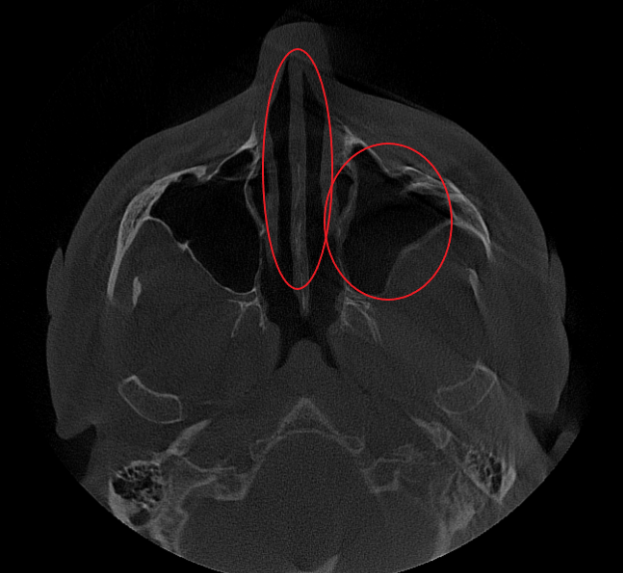

- Компьютерная томография (КЛКТ) околоносовых пазух и височных костей: Этот высокоинформативный метод диагностики объективно показал искривление носовой перегородки вправо, субтотальное снижение пневматизации (воздушности) левой верхнечелюстной пазухи, что свидетельствовало о хроническом воспалительном процессе. Костно-деструктивных изменений не выявлено.

- Хронический левосторонний верхнечелюстной синусит (J32.0). Длительное воспаление слизистой оболочки левой гайморовой пазухи, подтвержденное КТ.

Послеоперационный период протекал гладко. Проводились регулярные туалеты полости носа, промывание оперированной пазухи, назначались средства для увлажнения и регенерации слизистой оболочки, а также местная антибактериальная терапия. По результатам оперативного лечения носовое дыхание было полностью восстановлено, признаки активного воспаления купированы. Спустя 1.5 месяца после проведенного оперативного лечения проведено КТ околоносовых пазух в динамике, что отражает промежуточный результат оперативного лечения. На снимках: Перегородка носа располагается по центру, оперативно созданное соустье левой верхнечелюстной пазухи функционирует, пневматизация левой верхнечелюстной пазухи значительно улучшилась. Окончательный результат можно будет оценить через 3 месяца после проведенной операции, и при полной пневматизации левой верхнечелюстной пазухи пациент сможет приступить к установке зубных имплантов в верхнюю челюсть слева.